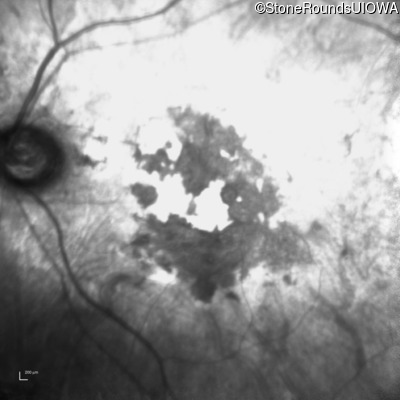

Fundus Photography - Left - Count Fingers 2'

Exemplar